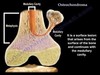

Describe an osteochondroma

- Benign or malignant:

- Typical patient:

- Common sites:

- Significance:

Osteochondroma

- Benign or malignant: Benign

- Typical patient: Males <25 y/o

- May arise after trauma or radiation

- Common sites: Distal femur, proximal tibia, arises from metaphysis

- Significance: Most common benign bone tumor

Good prognosis - rarely transforms to a chondrosarcoma

- Cap > 2 cm suggests malignant transformation

All statements are true of osteochondroma except:

- Recurrences may occur if the cartilaginous cap is not completely excised.

- Radiologically and grossly, the tumor projects away from the joint space.

- The cartilaginous cap exhibits microscopic features similar to the cartilage composing the growth plate.

- Presence of a cartilaginous cap >2cm, especially in an adult, is worrisome for sarcomatous transformation.

- In Multiple Hereditary Exostoses (Osteochondromatosis), the incidence of malignant transformation of the cartilaginous cap is over 50%

E.

In Multiple Hereditary Exostoses (Osteochondromatosis), the incidence of malignant transformation of the cartilaginous cap is over 50%

What kind of bone tumor is shown in this x-ray?

Osteochondroma

- Cartilagionous cap on a bony stalk continuous with the medulla of the bone

- Looks like an ice cream cone